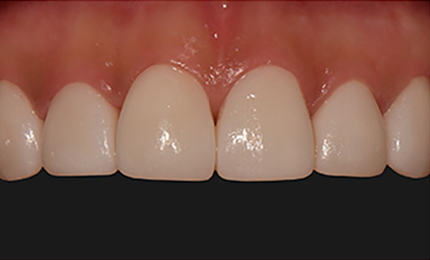

• 시술전

최소삭제 0.1mm - 0.2mm, 최대 0.3mm

시술 후